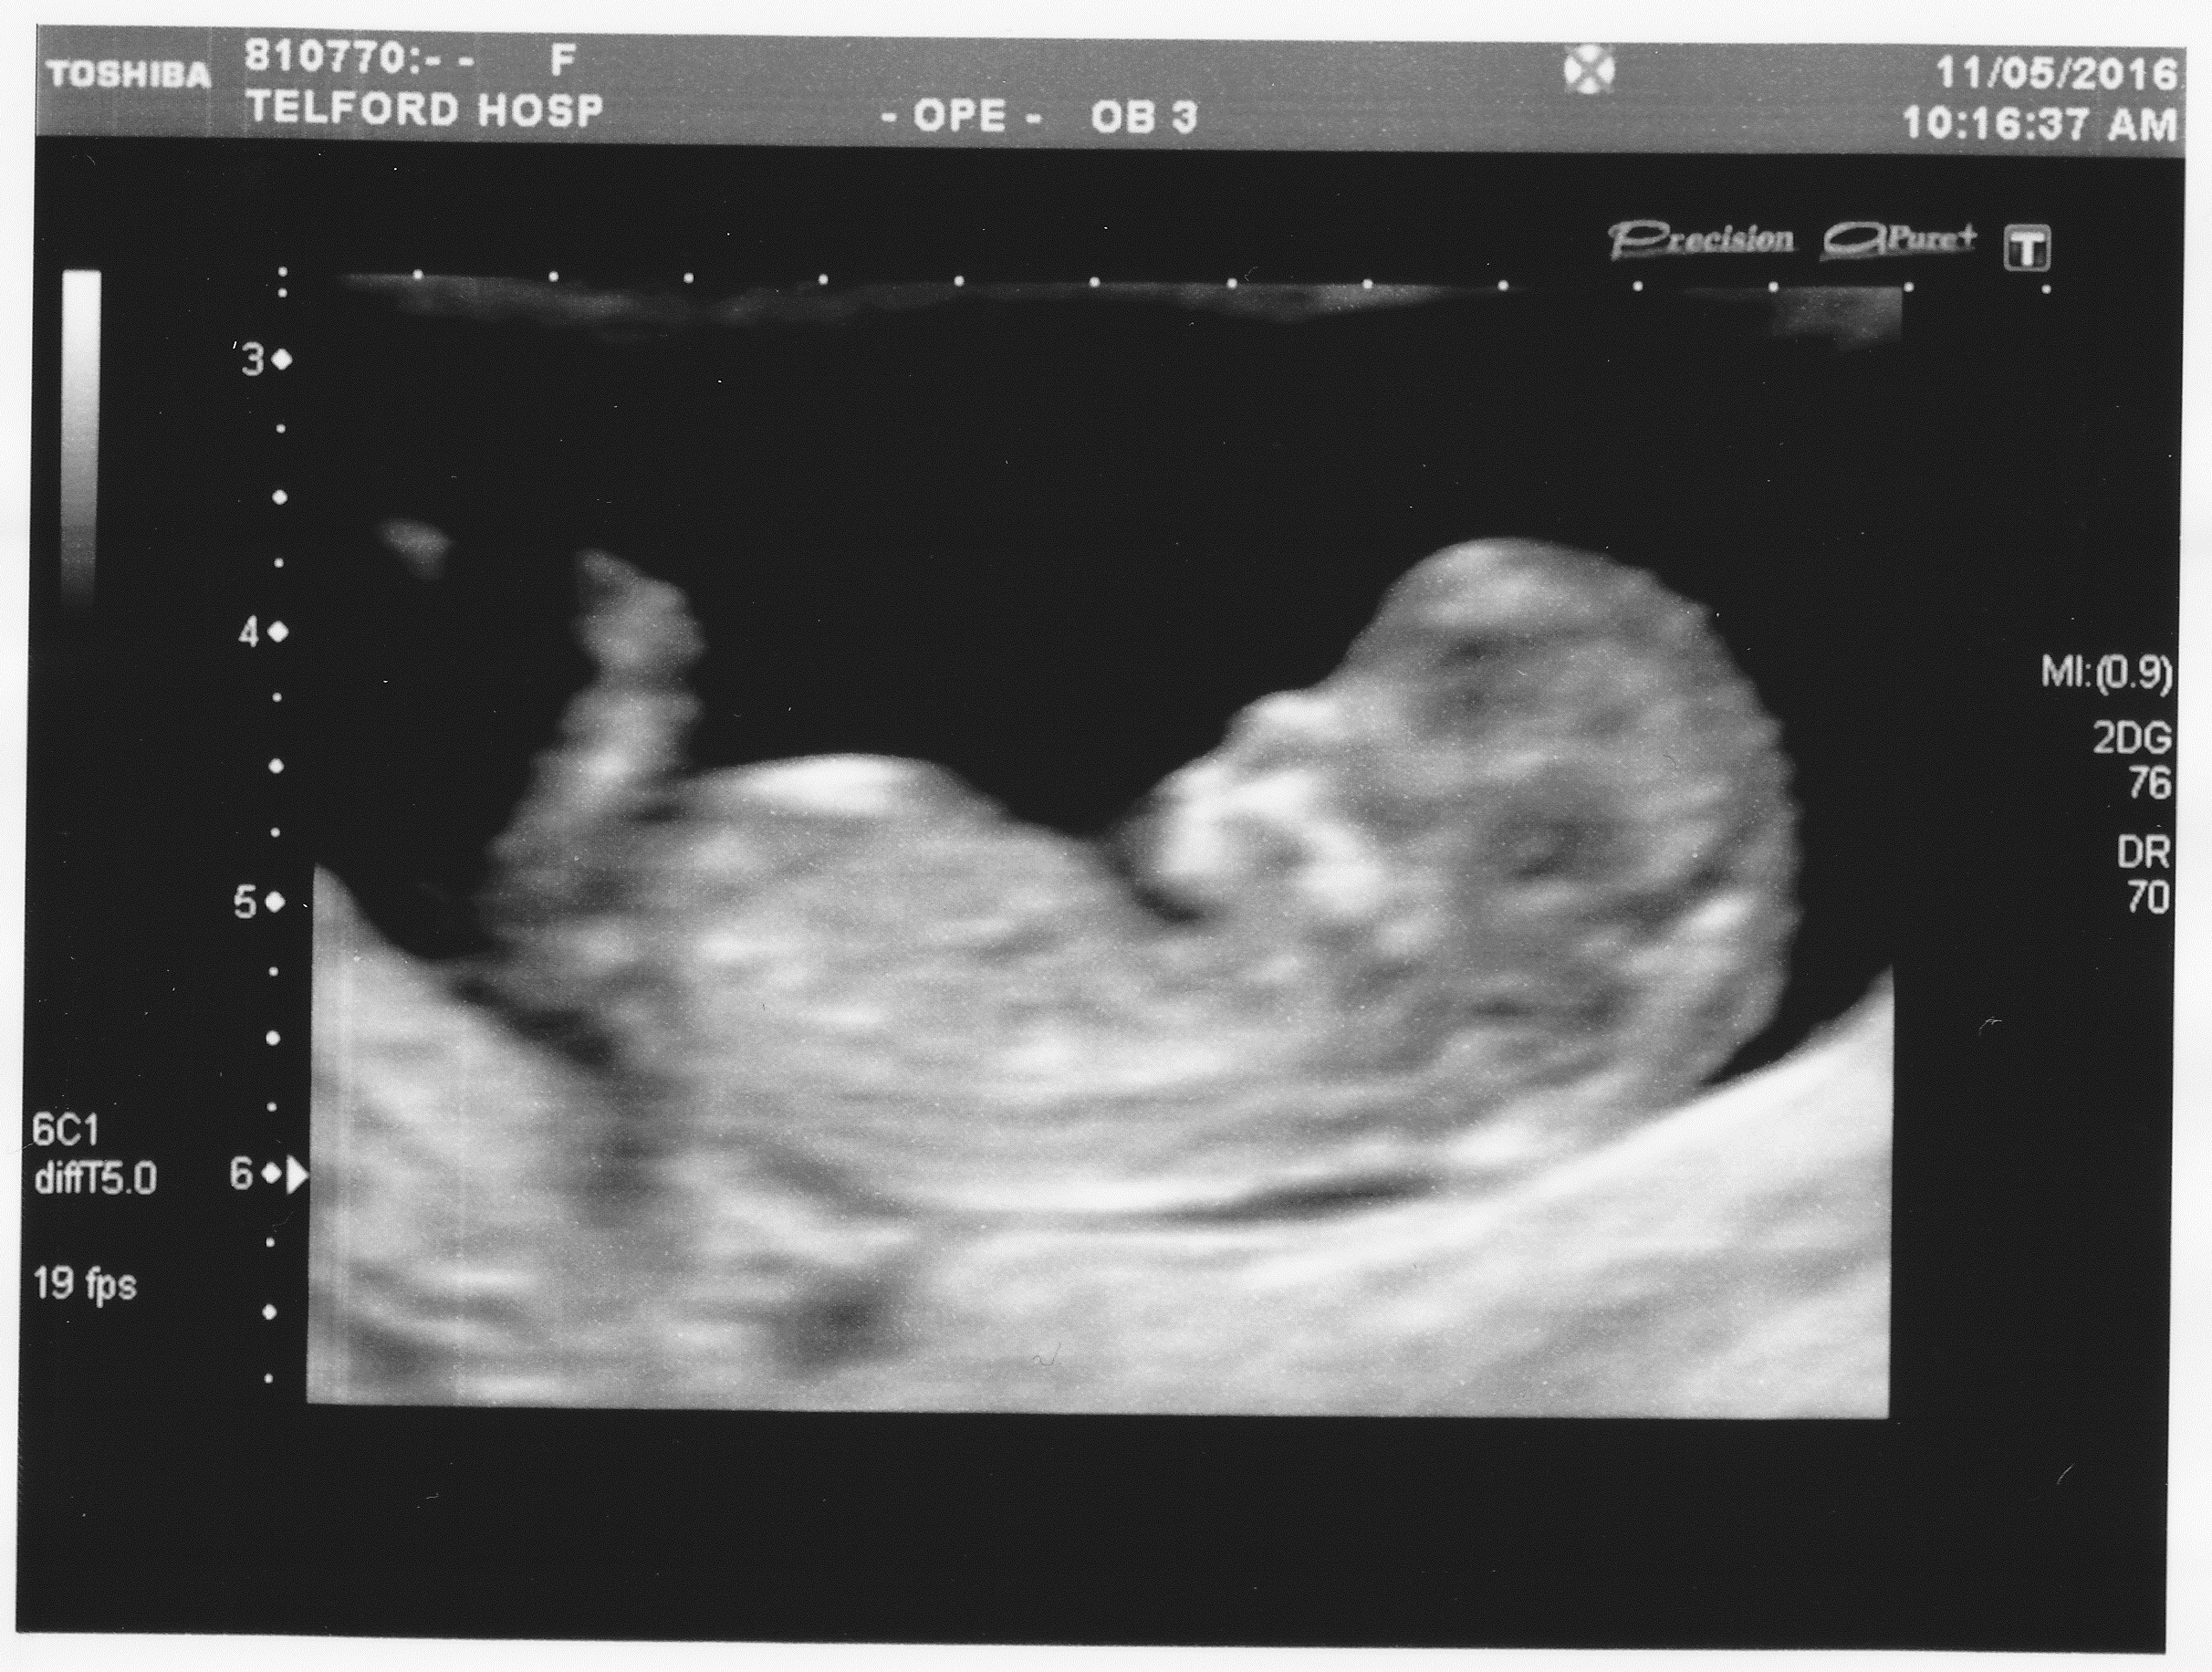

Attachment 32321

12 week scan above ^